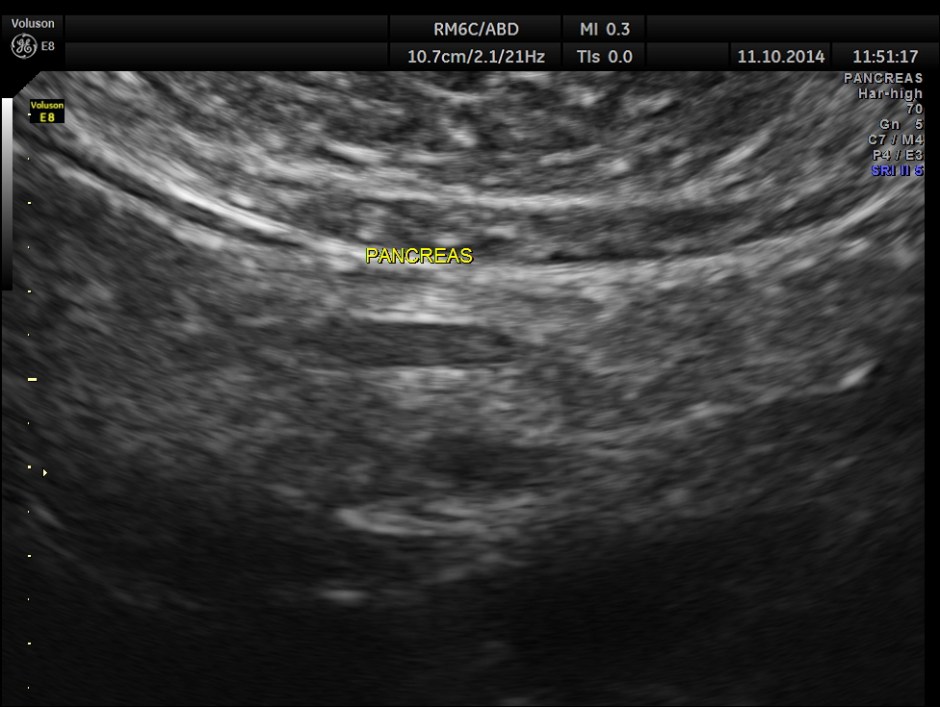

The spleno portal vein is just mildly dilated.